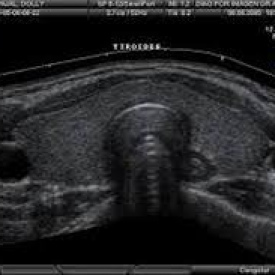

Ecografia de tiroides, cuello. Ecografias Bogota (Mandalay)

Bogotá, Avenida de las Américas # 78 - 11 COMPCASA IPS, Consultorio # 3 (frente a la Estación de Transmilenio Banderas)

$90000 |